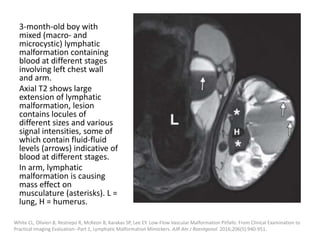

3-month-old boy with

mixed (macro- and

microcystic) lymphatic

malformation containing

blood at different stages

involving left chest wall

and arm.

Axial T2 shows large

extension of lymphatic

malformation, lesion

contains locules of

different sizes and various

signal intensities, some of

which contain fluid-fluid

levels (arrows) indicative of

blood at different stages.

In arm, lymphatic

malformation is causing

mass effect on

musculature (asterisks). L =

lung, H = humerus.

White CL, Olivieri B, Restrepo R, McKeon B, Karakas SP, Lee EY. Low-Flow Vascular Malformation Pitfalls: From Clinical Examination to